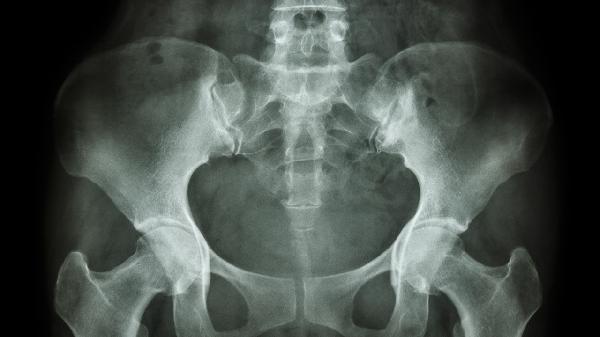

腎透明細胞癌主要病因可能與遺傳因素、環(huán)境因素、肥胖、高血壓以及獲得性腎囊腫等因素有關(guān)。腎透明細胞癌是腎癌中最常見(jiàn)的病理類(lèi)型,通常表現為血尿、腰痛和腹部腫塊等癥狀。

終末期腎病患者透析治療3-5年后可能出現獲得性腎囊腫,囊腫上皮細胞可能發(fā)生惡性轉化。此類(lèi)患者每6-12個(gè)月需進(jìn)行增強CT檢查,若發(fā)現囊壁增厚或實(shí)性成分應及時(shí)干預。